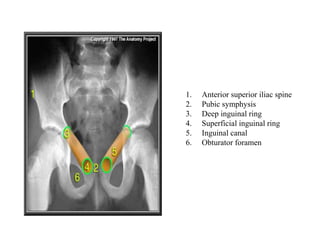

1. Anterior superior iliac spine

2. Pubic symphysis

3. Deep inguinal ring

4. Superficial inguinal ring

5. Inguinal canal

6. Obturator foramen